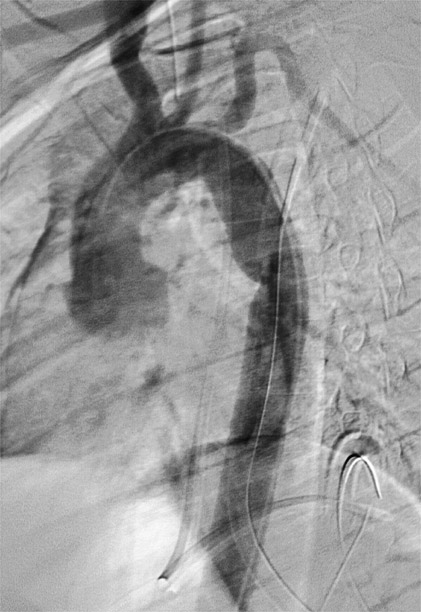

Gallery Blunt Chest Trauma Tr Aortic Injury Case 3b

Case 3b